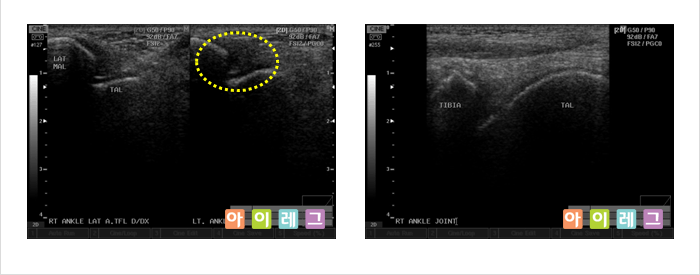

근골격계 초음파는 비전리 방사선의 한 종류인 초음파를 이용하여 영상을 만들어 냅니다. 초음파는

환자에 미치는 통증이나 방사선 노출이 전혀 없는 안전한 검사방법으로 관절,

연골, 인대, 건(힘줄), 점액낭, 근육, 신경 등 우리 몸을 움직이는 근골격계 구조물들의

이상(물이 차거나 염증 혹은 손상이 생긴 경우)을 진단하는 검사입니다. 환자의 진찰과

동시에 간편하게 시행할 수 있고, X-ray 등 방사선

검사로서 확인할 수 없는 경우 진단이나 치료에 도움이 됩니다.

또한, 근관절 정밀영상에 이용되는 고가의 MRI(자기공명영상)검사에 비해

저렴한 비용으로 시행할 수 있다는 장점이 있습니다.

* 위 영상은 모두 아이레그 의원에서 직접 검사한 영상 입니다.